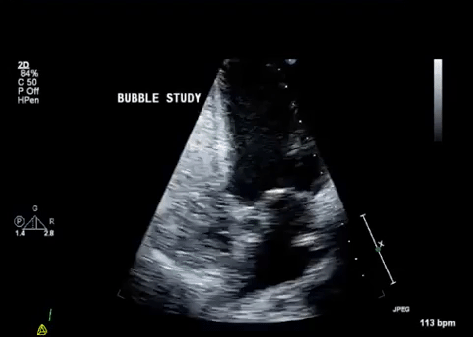

- Transthoracic contrast echo (TTCE): Can be used to demonstrate presence of intrapulmonary shunts supportive of presences of IPVDs

- Concept of bubble study: Shooting agitated saline (with bubbles into the vasculature

- Bubbles visible in the R heart chambers, should not be visible in the left heart chambers.

- If presence of bubbles in the left: This is indicative of a shunt:

- Intracardiac shunt: bubbles seen within 1 beat

- Intrapulmonary shunts: bubbles seen after 3-8 beats.

Echo demonstrating intrapulmonary shunting (see bubbles crossing over from the right to the left)